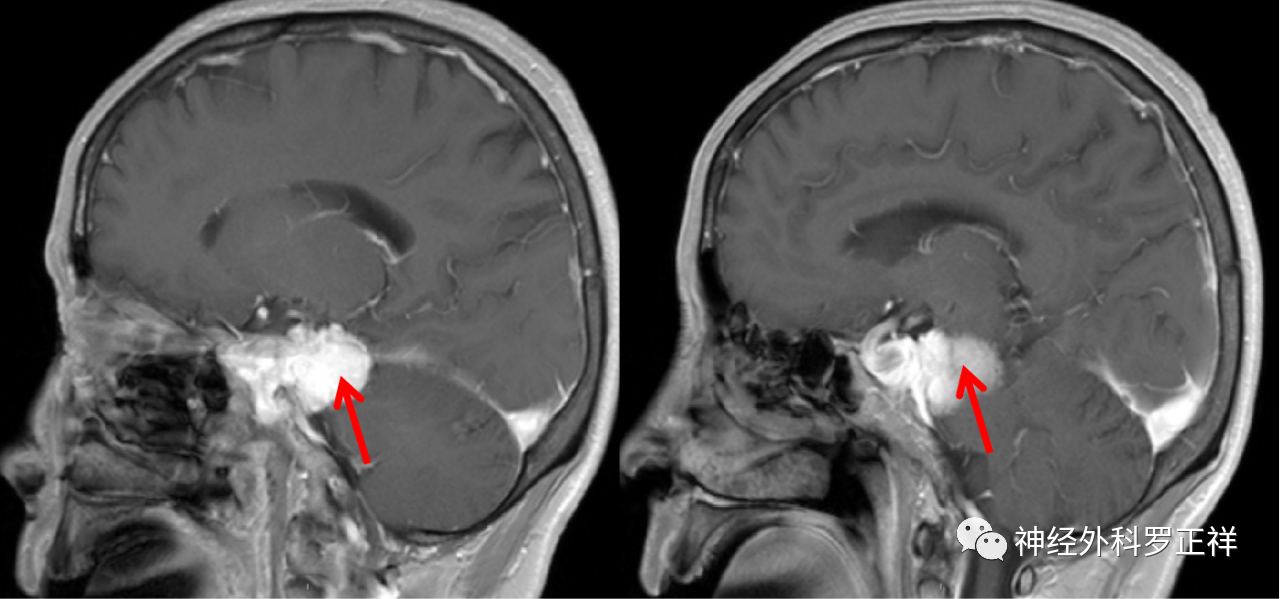

术前磁共振检查诊断:右侧岩尖脑膜瘤、继发性右侧TN;

术前MRI提示肿瘤位于右侧岩尖,压迫脑干及三叉神经。

术前磁共振轴位增强

术前磁共振矢状位增强